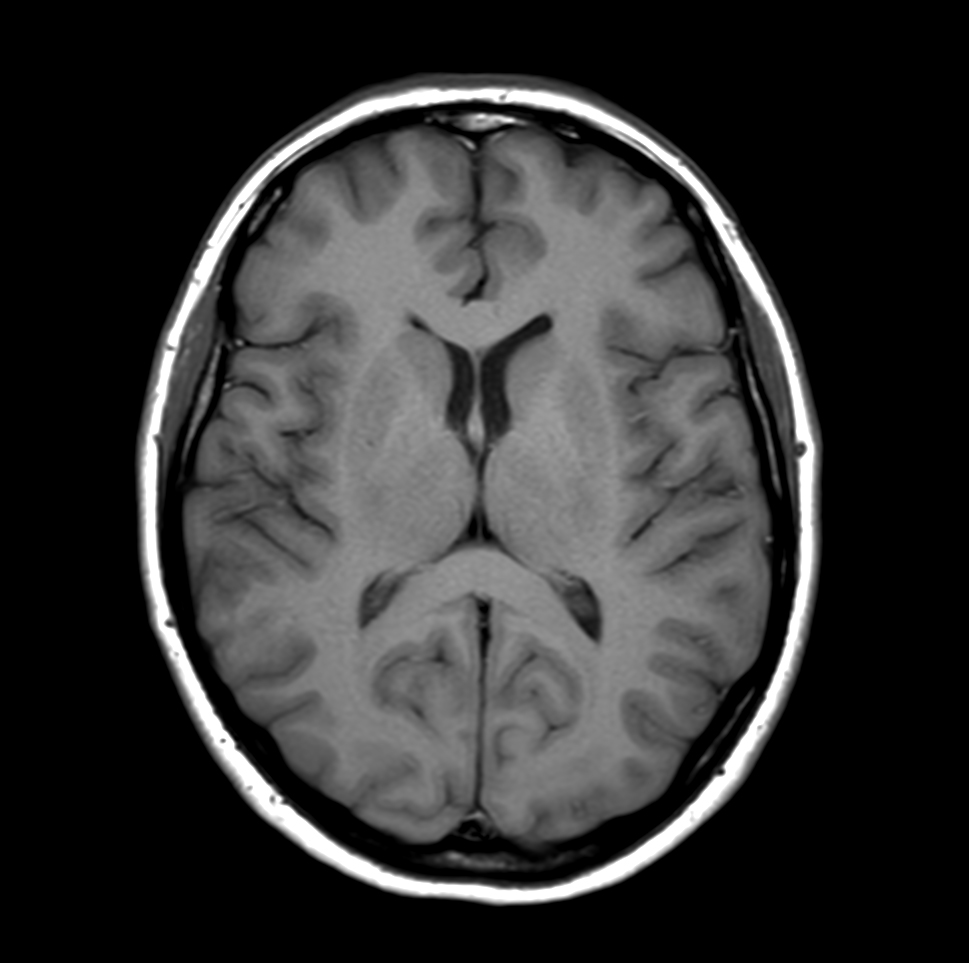

Axial T1w SE

Axial T1w FFE